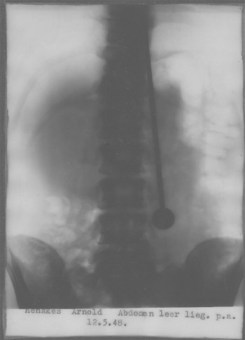

אך מההדגמות כמובן שלא ניתן להתעלם. ארנולד שיתף פעולה עם הרופאים באופן מלא. רבים בדקו אותו ונדהמו (לסרטון לחצו כאן). כאן תוכלו לראות אותו נכנס לחדר צילומי הרנטגן כשהמוט כבר תקוע בגופו. נראה כי מוטות אכן מפלחים את גופו ללא שניכרים סימני כאב על פניו, ללא זיהומים משמעותיים וללא דימום מאסיבי.

הפגיון הקטלני, יום לפני שהוצא בניתוח

(ויומיים לפני קום מדינת ישראל)

לגבי צילומי הרנטגן – צילומי רנטגן הינם דו מימדיים. אפשר להניח אדם על שולחן הרנטגן ואת החרב מתחת לשולחן או מתחת למזרן, אבל בדרכה של הקרן. מי שמביט בזה מהצד לא יראה את החרב אבל בצילום היא תצא בבירור. בדיקות מודרניות כמו CT, שהינו תלת מימדי, היו חושפות את התרמית מיד אם החרב לא עוברת בתוך הקרביים ממש. אולי זו הסיבה שמאז שנות ה-80 (בהם יצא ה-CT לשימוש נרחב) לא שמענו יותר על תופעה כזו.